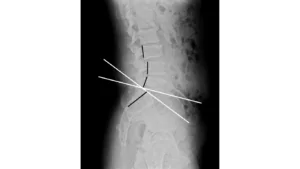

③矯正・アジャストメント

上記の検査で矯正すべき圧迫箇所を特定し矯正します。患者様1人1人に合わせた無理のない矯正を行います。